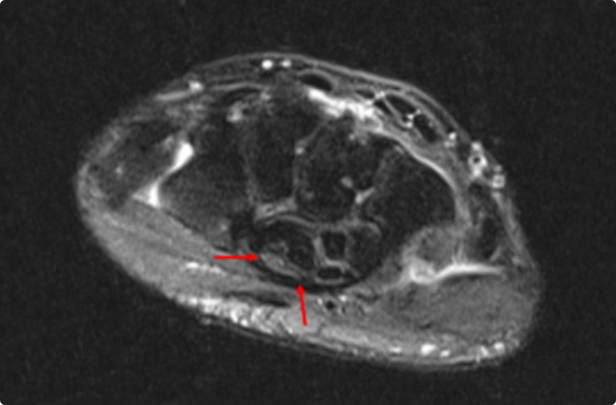

MRI 에서 다음과 같이 신경이 눌려 있고, 횡수근 인대 전단계에는 신경이 부어 있는 모습이 관찰되면

중증의 손목터널증후군으로 판단할 수 있습니다.